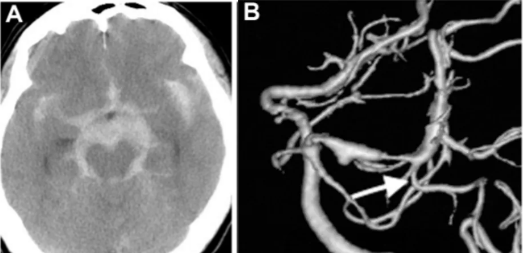

47 岁男性患者,确诊蛛网膜下腔出血(Hunt-Hess & Kosnic 3 级),影像检查显示伴有左侧脑桥前池增厚(图A)。

初次就诊时,3D-CTA或 DSA 均未发现扩张或血管病变。

出血第18天后,延迟血管造影显示左侧 P1-P2 段有一个不断增长的夹层动脉瘤,并具有狭窄特征(图B),PTA从狭窄病变的远端部分分支(箭头)。